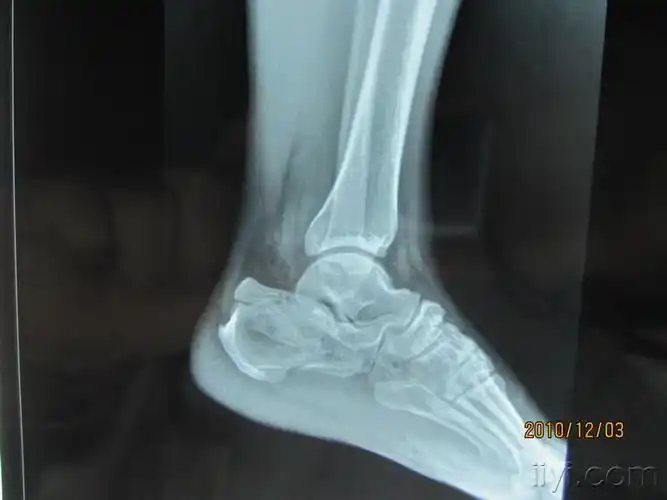

左跟骨粉碎性骨折请教手术方案